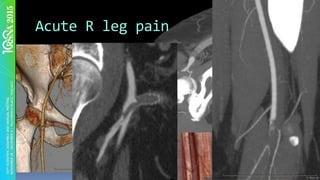

Acute	R	leg	pain